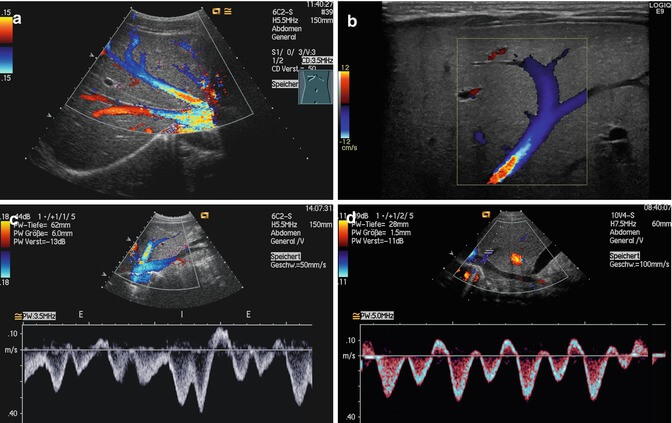

Abdominal Doppler ultrasound imaging procedures, which enable the examination of organs such as kidney, gall bladder, adrenal glands, pancreas, midline vascular structures, spleen, liver, are performed in a very simple and comfortable way. While many patients want to have this examination, they wonder what the procedure is and how it is done.

After the examination, sound waves are used to follow the patients safely. These painless and harmless imaging systems help to have homogeneous size of the examined organ and to have information about the structure of the vessels.